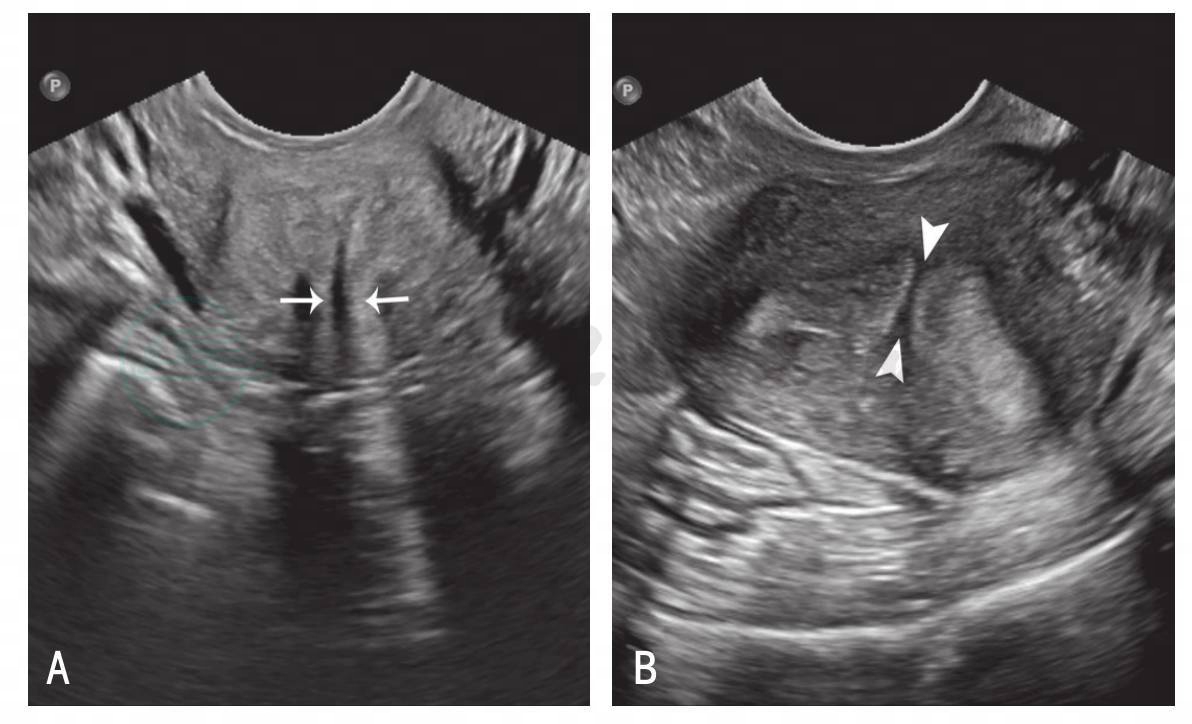

图3-7 完全性纵隔子宫声像

A.宫颈冠状切面;B.宫体冠状切面;箭:宫颈管间间隔;箭头:子宫体间间隔